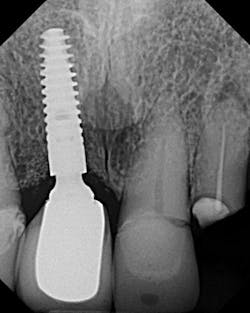

4. Mixing parts from different companies can cause component misfit. Third-party parts from “cheaper” implant companies may be used to lower cost, but they don’t always result in complete fit. In fact, implant companies that warranty their parts for replacement often void this warranty if those parts are used in combination with parts from another company (figure 3).